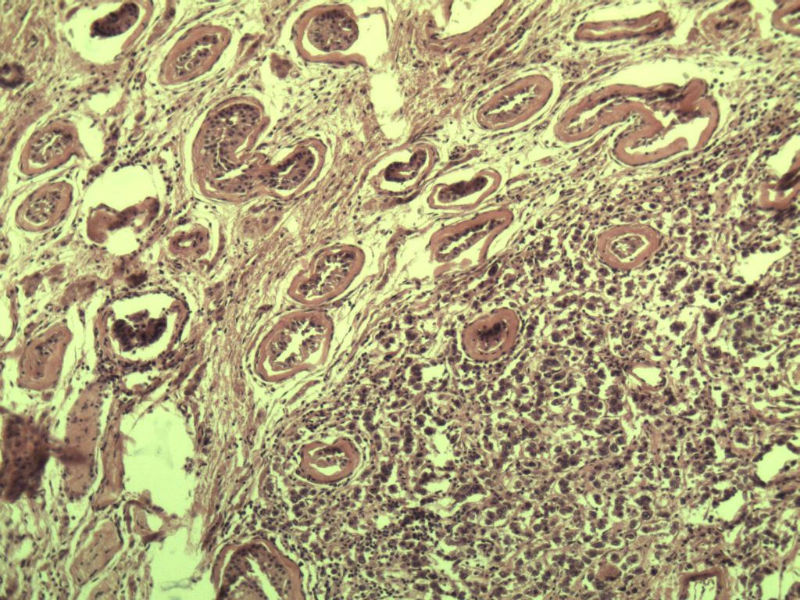

男 27岁 腹腔隐睾 5*3*2 cm, 切面灰红灰黄、实性、质中,请各位老师看看,是精原细胞瘤吗?感觉不像.